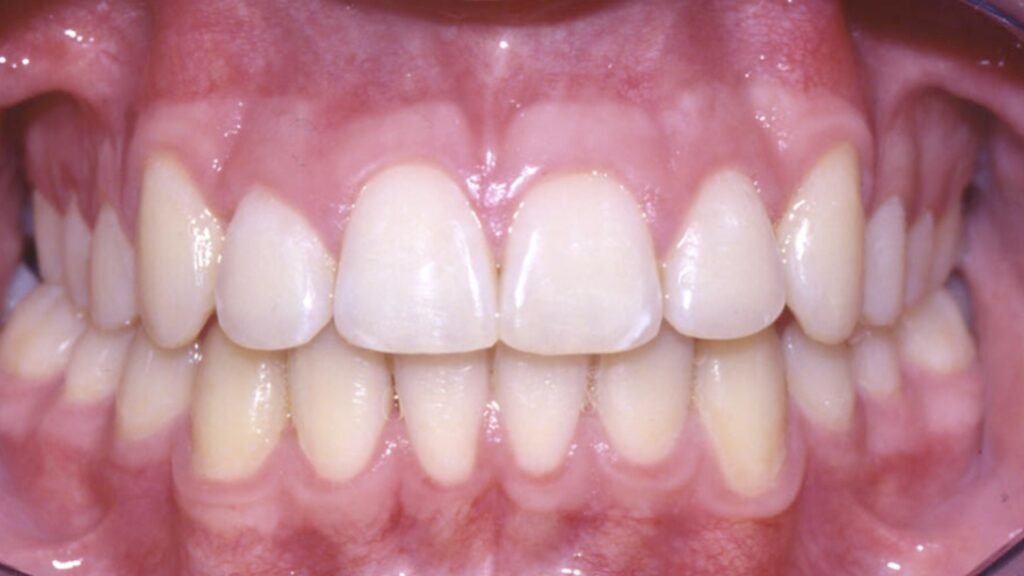

- Le déterminant antérieur ou guide antérieur est constitué par les contacts de l’arcade mandibulaire avec le secteur incisivo-canin supérieur

- Guide antérieur fonctionnel

- L’objectif de la prothèse partielle est non seulement de remplacer les dents manquantes mais également d’obtenir un optimum physiologique avec pour aboutissement une occlusion équilibrée. Celle-ci suppose :

- Un contrôle neuromusculaire sans contrainte

- Une répartition harmonieuse de la charge occlusale.